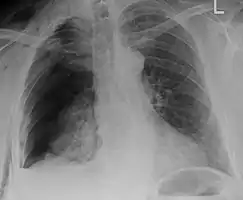

| An X ray showing multiple old fractured ribs of the person's left side as marked by the oval. | |

Right sided pneumothorax and rib fractures